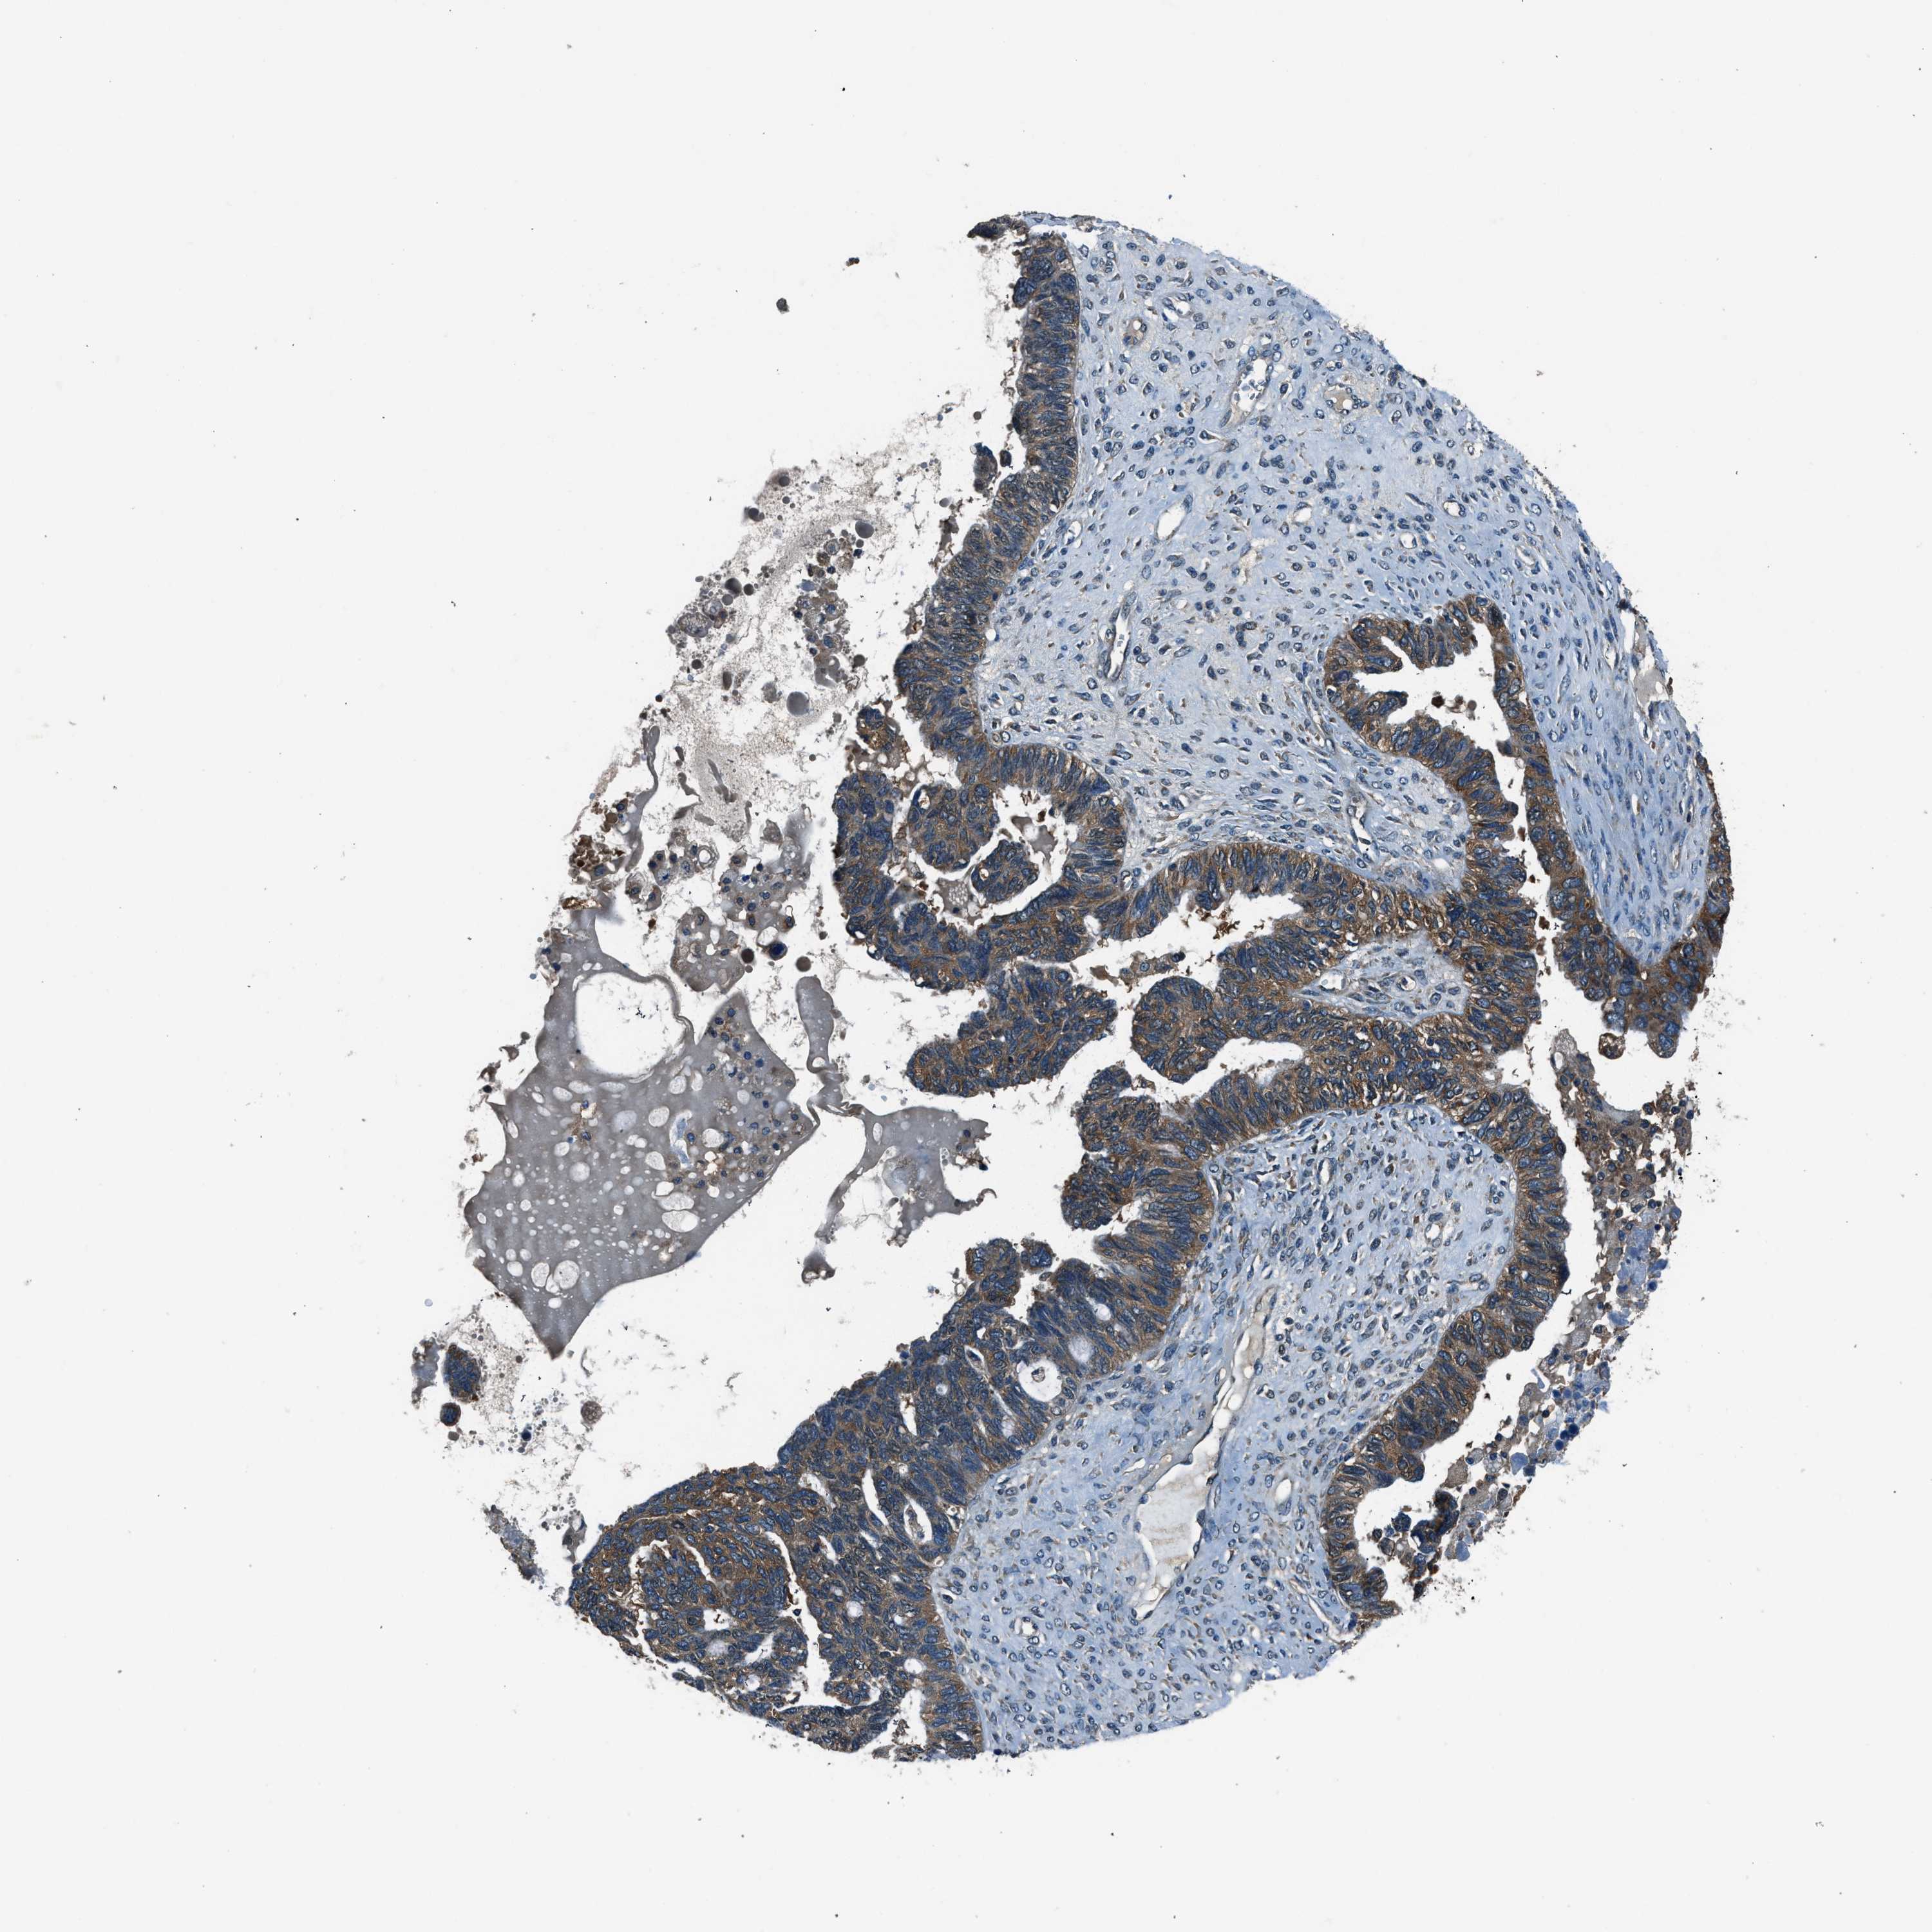

OVARIAN CANCER - Protein expressioni

A mouse-over function shows sample information and annotation data. Click on an image to view it in a full screen mode. Samples can be filtered based on level of antibody staining by selecting one or several of the following categories: high, medium, low and not detected. The assay and annotation is described here.

Note that samples used for immunohistochemistry by the Human Protein Atlas do not correspond to samples in the TCGA dataset.

Antibody stainingi

Antibody staining in the annotated cell types in the current human tissue is reported as not detected, low, medium, or high, based on conventional immunohistochemistry profiling in selected tissues. This score is based on the combination of the staining intensity and fraction of stained cells.

Each image is clickable and will lead to virtual microscopy that enables deeper exploration of all samples and also displays staining intensity scores, fraction scores and subcellular localization as well as patient and tissue information for each sample.

Antibody HPA016649

Antibody HPA018152

Cystadenocarcinoma, serous, NOS

Carcinoma, endometroid

Cystadenocarcinoma, mucinous, NOS

Carcinoma, NOS